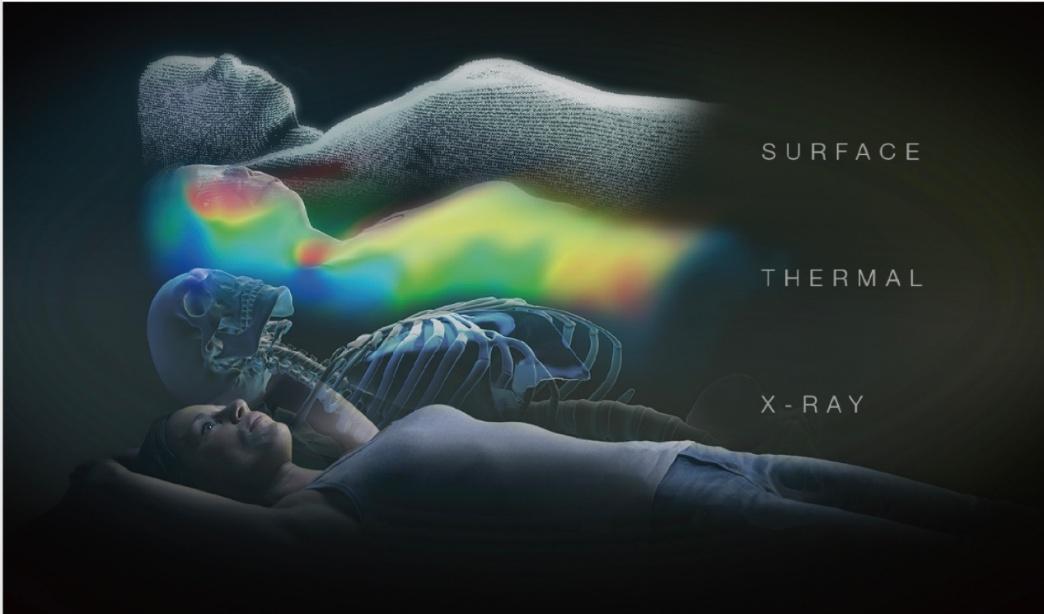

SGRT体表面誘導放射線治療システム(ExacTrac Dynamic Surface)

SGRT(Surface Guided Radiation Therapy)は、患者さんの体表面をカメラで三次元的に取得し、その形状を基準データ(治療計画CTから生成された体表面)と比較することで、患者さんの位置ずれを非接触で高精度に検出する技術です。

ExacTrac Dynamic Surface では、3Dステレオカメラ、構造化光、赤外線サーマルカメラなどを用いて体表面をリアルタイムにスキャンし、数十万点に及ぶ三次元表面データを取得します。これにより、体表面の形状と温度情報を組み合わせた高精度な位置追跡が可能となります。

さらに、X線画像による内部構造の確認を組み合わせることで、骨構造などの内部位置情報を含めた精密な位置合わせが可能です。これにより、従来の皮膚マークを使用しない治療が可能となり、特に乳房温存照射において患者さんの精神的負担の軽減に貢献します。